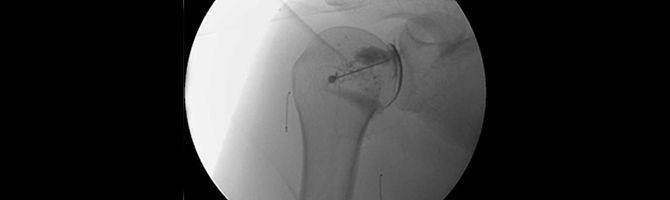

Calcific Tendonitis X-ray

Calcific tendonitis can be diagnosed through X-ray imaging, which reveals the calcifications formed in the tendon.